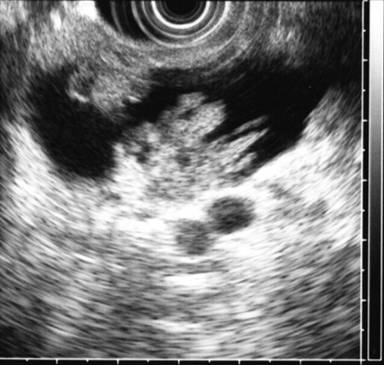

The EUS appearance of mucinous cystic neoplasm is variable. They are commonly associated with a visible wall and septations of variable thickness, and peripheral calcifications can be seen in some cases (Figures 1 and 2) [43]. Invasive malignancy has been associated with the presence of thick or irregular cyst wall, intramural nodules or solid components and larger cyst size (Figure 3) [14]. EUS-FNA cytology could reveal columnar epithelial cells in up to half of the patients in association with extracellular mucin [34, 46]. Mucin is frequently identified on EUS-FNA of mucinous cystic neoplasm and cyst fluid is typically clear with elevated CEA levels and low amylase. Mucinous cystic neoplasms are premalignant lesions but the risk of malignant degeneration is likely less than that of IPMN [45]. The risk of malignancy in these tumors described in a series of 163 patients was found to be 17.5% [47]. Therefore, surgical resection is recommended for all surgically fit patients. The prognosis after surgery for mucinous cystic neoplasm that have not undergone malignant transformation is excellent and the 5-year survival for mucinous cystadenocarcinomas post resection exceeds 60% [6, 48].

Figure 1. EUS findings in a 42-year-old female patient with a mucinous cystic neoplasm in the body of the pancreas. A cyst wall is present in addition to one tangential thin septum. The adjacent parenchyma appears unremarkable. No FNA was performed in this case and the patient was referred to surgery. |